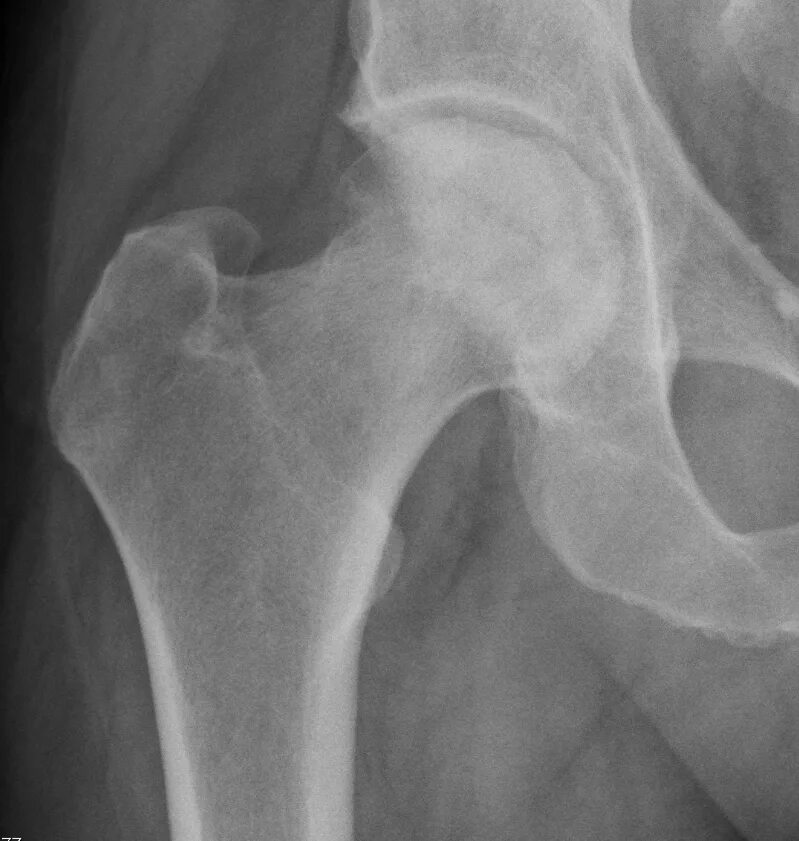

Некроз головки тазобедренного сустава 2